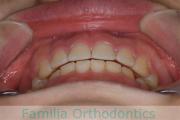

No.23V-385

- 主な症状:

- 叢生

- 年齢:

- 17歳

- 性別:

- 女性

- 抜歯部位

- 上:

- 44

- 下:

- 8448

- 主な使用装置:

- FEA 022

- 治療にかかった費用:

- 90万円

前歯のゆがみ、ズレがあるのを治したいということで来院されました。上下左右から小臼歯を抜歯して、マルチブラケット法にて治療をしました。1年8か月、20回程度の通院をしていただきました。叢生(でこぼこ、凹凸、ガタガタ)が強いため、保定をしっかりしないと後戻りのリスクがやや高いケースといえます。

- ≫治療前

-

上顎

下顎

前歯の関係など